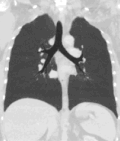

A CT scan can be used for detecting both acute and chronic changes in the lung parenchyma, the tissue of the lungs.[66] It is particularly relevant here because normal two-dimensional X-rays do not show such defects. A variety of techniques are used, depending on the suspected abnormality. For evaluation of chronic interstitial processes such as emphysema, and fibrosis,[67] thin sections with high spatial frequency reconstructions are used; often scans are performed both on inspiration and expiration. This special technique is called high resolution CT that produces a sampling of the lung, and not continuous images.[68]

Vascular Imaging

Computed tomography angiography (CTA) is a type of contrast CT to visualize the arteries and veins throughout the body.[111] This ranges from arteries serving the brain to those bringing blood to the lungs, kidneys, arms and legs. An example of this type of exam is CT pulmonary angiogram (CTPA) used to diagnose pulmonary embolism (PE). It employs computed tomography and an iodine-based contrast agent to obtain an image of the pulmonary arteries.[112][113]